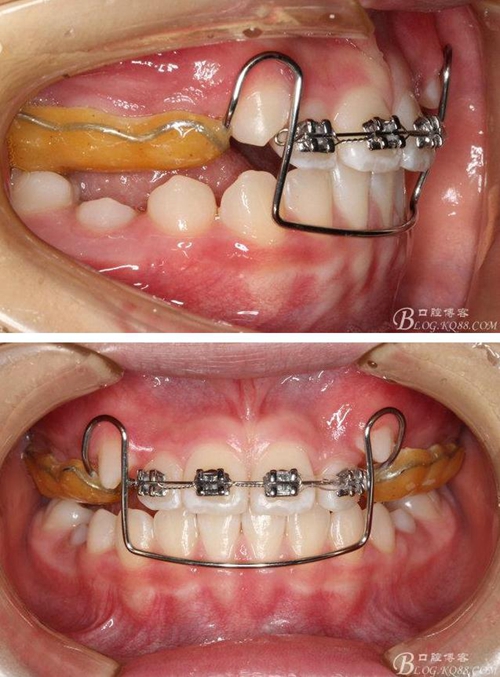

矯治第4個月復(fù)診:前牙反咬合進(jìn)一步改善。拆下固定式Activator,上頜前牙2-2粘貼托槽,排齊前牙并進(jìn)一步解決反咬合。這時發(fā)現(xiàn):后牙咬合不緊。如不處理必然會出現(xiàn)前牙創(chuàng)傷咬合,如何解決呢?

將拆下來的Activator清潔干凈,變?yōu)榭烧C治器,繼續(xù)佩戴,同時逐步降低樹脂咬合面高度。